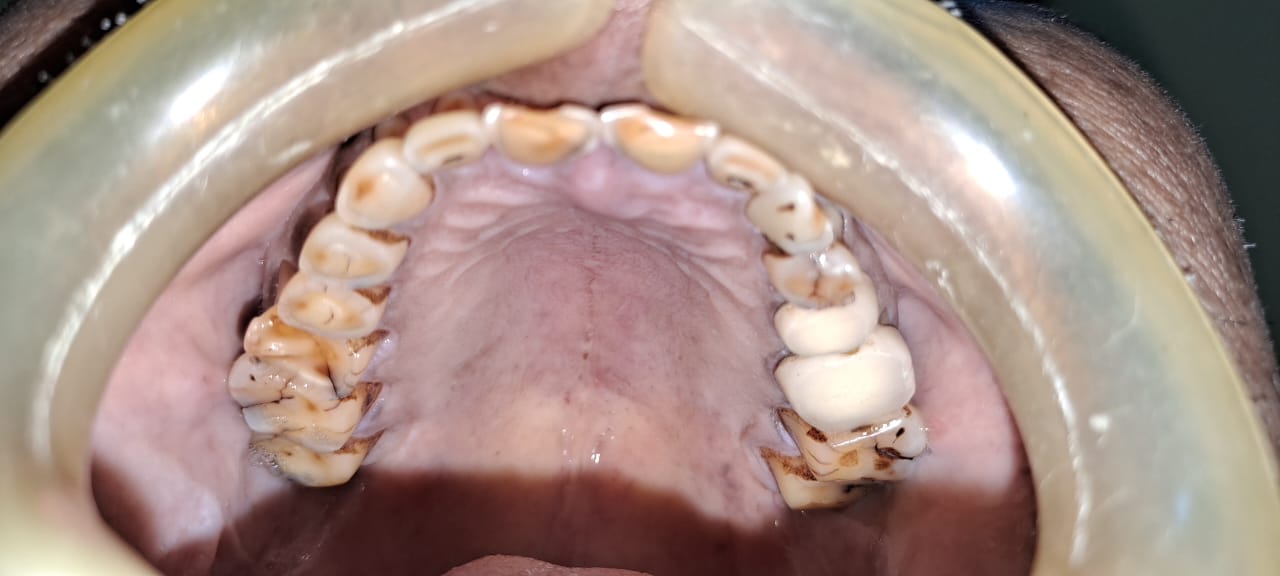

Case Scenario 2 - Full Mouth Rehabitilation

Exciting News! Discover the Steps of Full Mouth Rehabilitation for a Dazzling Smile! Are parafunctional habits like kharra and ghutka taking a toll on your dentition? Say goodbye to improper chewing, loss of facial aesthetics, and digestive troubles with our expert team at Chintamani Dental Clinic!

Step 1: Accurate Diagnosis Using our in-house OPG, we pinpoint the issues to create a tailored plan just for you.

Step 2: State-of-the-Art Treatments Experience top-notch root canal treatments and effective temporization protocols for optimal oral health.

Step 3: Precise Impressions Utilizing cutting-edge scanning technology, we ensure accurate impressions for a perfect fit.